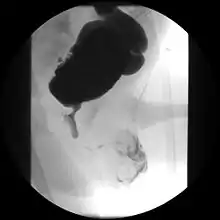

Ultrasound imaging can give information on the shape of the bladder, post-void residual volume, and evidence of kidney damage such as kidney size, thickness or ureteral dilation.[8] Trabeculated bladder on ultrasound indicates high risk of developing urinary tract abnormalities such as hydronephrosis and stones.[9] A voiding cystourethrography study uses contrast dye to obtain images of the bladder both when it is full and after urination which can show changes in bladder shape consistent with neurogenic bladder.[8]